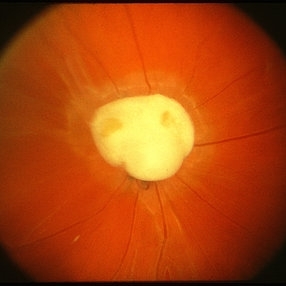

Toxocara Granuloma

Toxocara Granuloma

Feb 25 2013 by Henry J. Kaplan, MD

Toxocara granuloma of the optic nerve head.

Condition/keywords: ocular toxoplasmosis, toxocara granuloma, toxocariasis